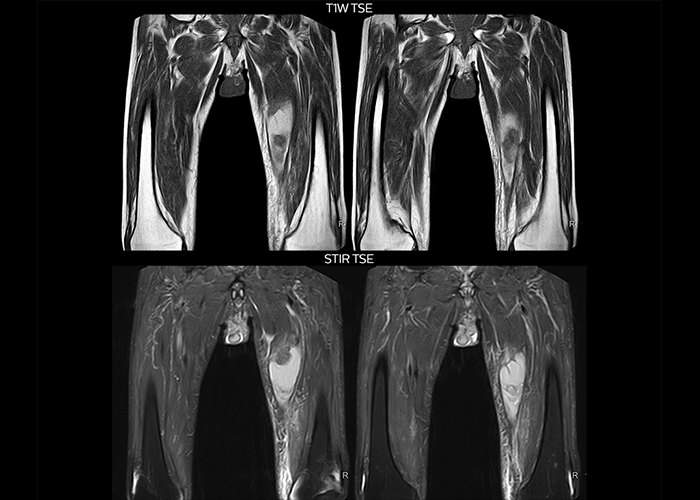

“On average, we scan about 80 patients per day, but on some days we scan well over 100 patients. The scanner is in use 7 days per week, operated 20 hours per day on week days and 8 hours per day in the weekend,” Mr. Tuna says. “To avoid coil changes we plan examinations of similar anatomies back to back, such as head and spine. Multiva helps us here a lot because coils don’t need to be changed frequently. Moreover, thanks to parallel imaging technology and 16-channel HeadSpineTorso and 8-channel MSK coils we are able to achieve excellent image quality. In this way Multiva helped us to increase both image quality and productivity.” “Neurological cases, such as brain and spine imaging, represent the largest share in our MR scanning, followed by musculoskeletal cases. In general, we use simple and basic imaging protocols. But occasionally, we use advanced techniques for problematic cases if necessary.

“Since we have Multiva, we have improved our workflow, because it has been so easy for our operators to learn and use Multiva. Our operators notice that the coils are lightweight and coils don’t need to be changed frequently. The user interface is easy to use. Features like this help us to scan a high number of patients. For instance, the musculoskeletal coils can be used interchangeably, and due to the user-friendly interface, the number of mistakes such as, for example, correct coil element selection has decreased significantly, because the system does it automatically by itself.” “Most important, Multiva satisfies our clinical imaging needs very well,” says Mr. Tuna. “Many features of Multiva have become similar to the Ingenia system. Even in more complex imaging such as abdominal and cardiac, the image quality and performance of Multiva is better than we expected. General surgeons and physicians from our hospital’s internal medicine department prefer to refer to us because of this.”

“Overall, Multiva provides what we need in term of patient needs and even potential needs,” says Mr. Tuna. “It allows us to scan a high patient volume and image a large variety of anatomies and conditions.” “Our goal is to achieve uncompromising quality based on universal standards, while solving clinically complex cases. Our Multiva scanner allows high productivity with fast imaging time, and allows us to make confident diagnoses in a broad range of cases.” “It’s an excellent multi-purpose scanner that satisfies all our MR imaging requirements in the hospital,” he concludes.